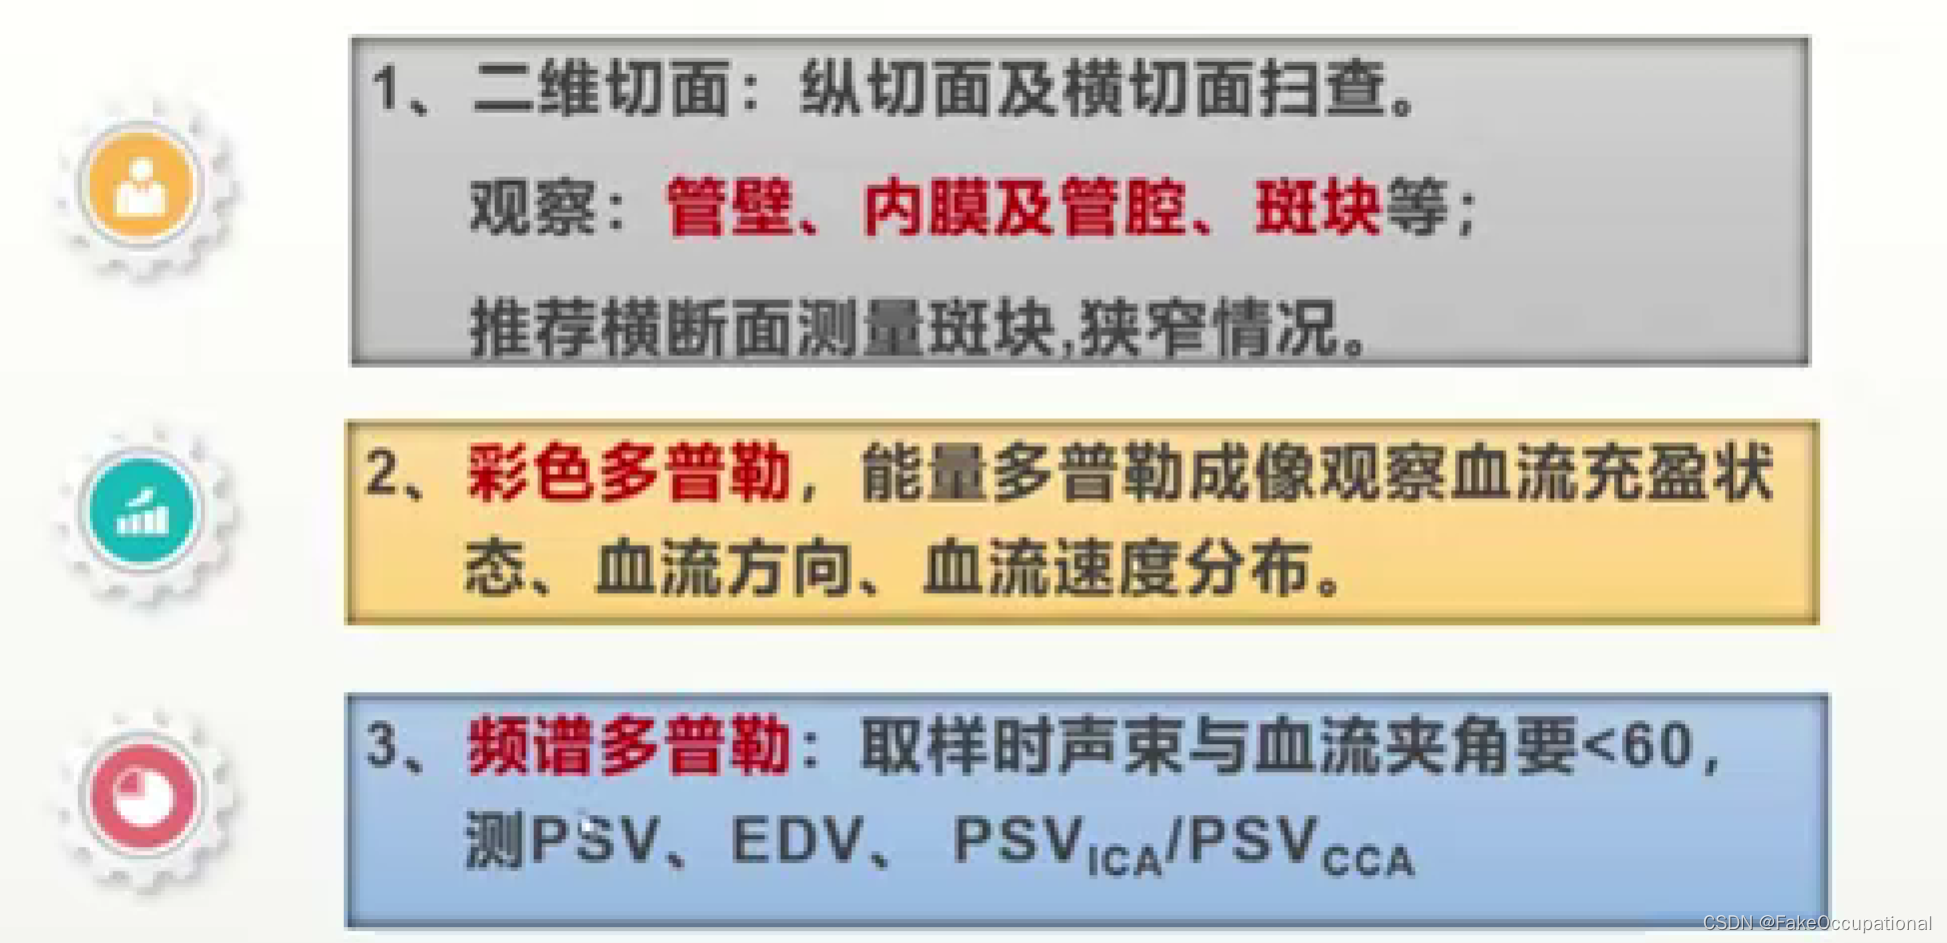

血管超声